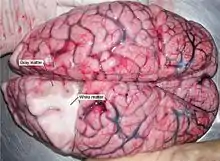

Au microscope, il existe des différences entre les neurones, les tissus du système nerveux central et le système nerveux périphérique. Le système nerveux central est divisé en matière blanche (ou substance blanche) et matière grise[8]. Celles-ci peuvent aussi être observées macroscopiquement sur les tissus du cerveau. La matière blanche est constituée d'axones et oligodendrocytes, tandis que la matière grise est constituée de neurones et les fibres amyéliniques. Les deux tissus comprennent un certain nombre de cellules gliales, qui sont souvent désignées comme supportant les cellules du système nerveux central. Les différentes formes de cellules gliales ont des fonctions différentes, certains agissant presque comme échafaudage pour permettre aux neuroblastes de grimper au cours de la neurogenèse, tandis que d'autres tels que les microglies sont une forme spécialisée de macrophages, impliqués dans le système immunitaire du cerveau[3]. Les astrocytes peuvent être impliqués à la fois dans la clairance des métabolites ainsi que dans le transport de carburant et de diverses substances bénéfiques pour les neurones du cerveau.

Le cerveau (comportant le cervelet ainsi que la mésencéphale et le rhombencéphale) se compose d'un cortex, composé de neurones constituant la matière grise, tandis qu'à l'intérieur, il y a plus de matière blanche. En dehors de la matière grise du cortex[8].